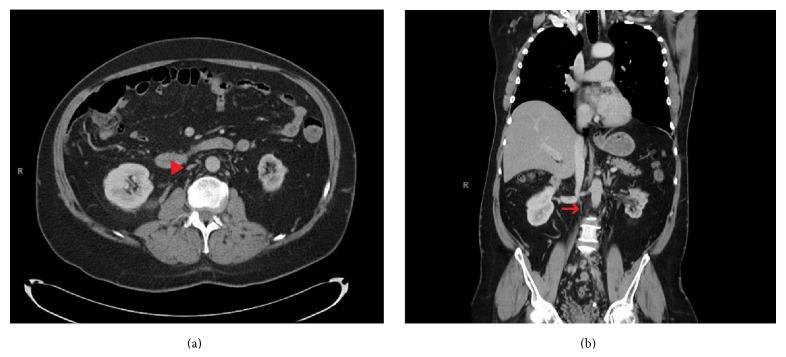

Inferior vena cava agenesis (IVCA) is a rare congenital anomaly that can be asymptomatic or present with vague, nonspecific symptoms, such as abdominal or lower back pain, or deep vein thrombosis (DVT). Here, we present a 55-year-old male who came with painless swelling and redness of his left lower limb. On examination, swelling and redness were noted extending from the left foot to the upper thigh; it was also warm compared to his right lower limb. Venous Doppler ultrasound was done which showed DVT extending up to the common femoral vein. Subsequently, computed-tomography (CT) of the chest and abdomen was done to exclude malignancy or venous flow obstruction; it revealed congenital absence (agenesis) of the infrarenal inferior vena cava (IVC).

下腔静脉发育不全(IVCA)是一种罕见的先天性异常,可能无症状,或表现为模糊、非特异性的症状,如腹痛或下背痛,或深静脉血栓形成(DVT)。在此,我们报告一名55岁男性,他因左下肢无痛性肿胀和发红前来就诊。检查时,发现肿胀和发红从左脚延伸至大腿上部;与右下肢相比,该部位也更温暖。进行了静脉多普勒超声检查,结果显示深静脉血栓形成延伸至股总静脉。随后,进行了胸部和腹部的计算机断层扫描(CT)以排除恶性肿瘤或静脉血流阻塞;结果显示肾下下腔静脉(IVC)先天性缺失(发育不全)。